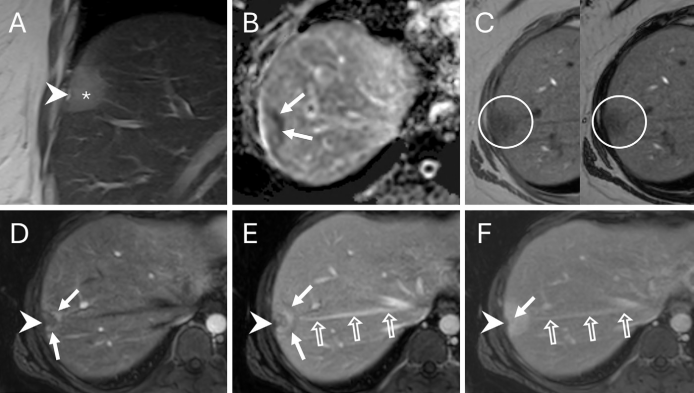

年轻女性多发肝占位:特殊的“棒棒糖”征象指引了怎样的罕见真相?

病史摘要:33岁女性患者,数月来右上腹间歇性不适,伴早饱、腹胀及恶心,症状反复后就诊。 诊疗过程:体格检查无明显异常。实验室检查肝功能及肿瘤标志物正常,尿妊娠试验阴性。腹盆部增强CT见肝内3个不明病灶;腹部MRI显示病灶有包膜皱缩、弥散受限等特征,出现“棒棒糖征”。主要诊断为肝上皮样血管内皮细胞瘤(EHE),鉴别排除转移瘤等疾病。经皮穿刺活检病理及免疫组化确诊EHE。随访8个月病灶大小